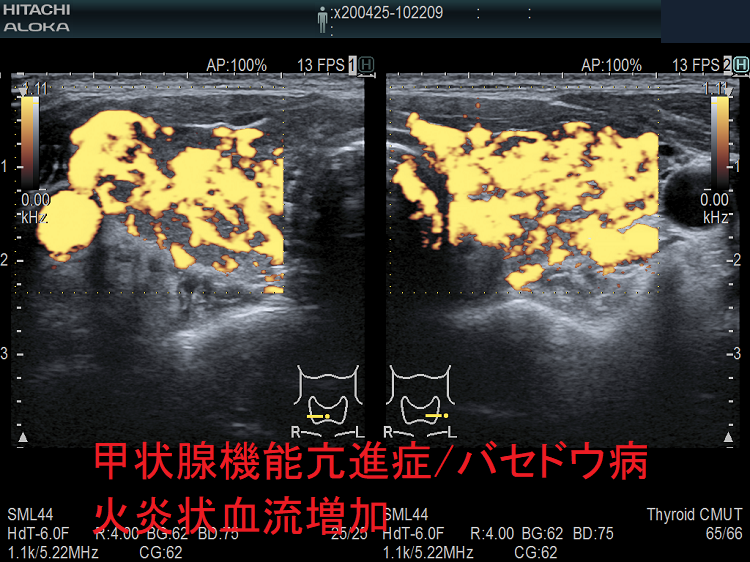

甲状腺機能亢進症バセドウ病 火炎状血流増加

甲状腺機能亢進症/バセドウ病の火炎状血流増加;著明な血管増殖のため甲状腺内の血流が増加します。

しかし、無痛性甲状腺炎でも、甲状腺機能低下症でも血流増加するため、これだけでは鑑別できません。

甲状腺機能亢進症 バセドウ病 火炎状血流増加

甲状腺機能亢進症/バセドウ病の火炎状血流増加